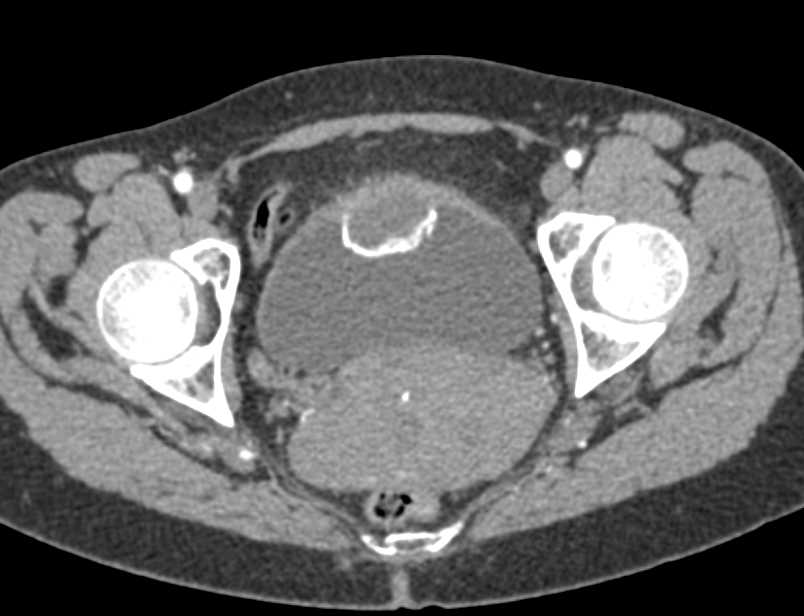

Urachal Carcinoma of the Bladder